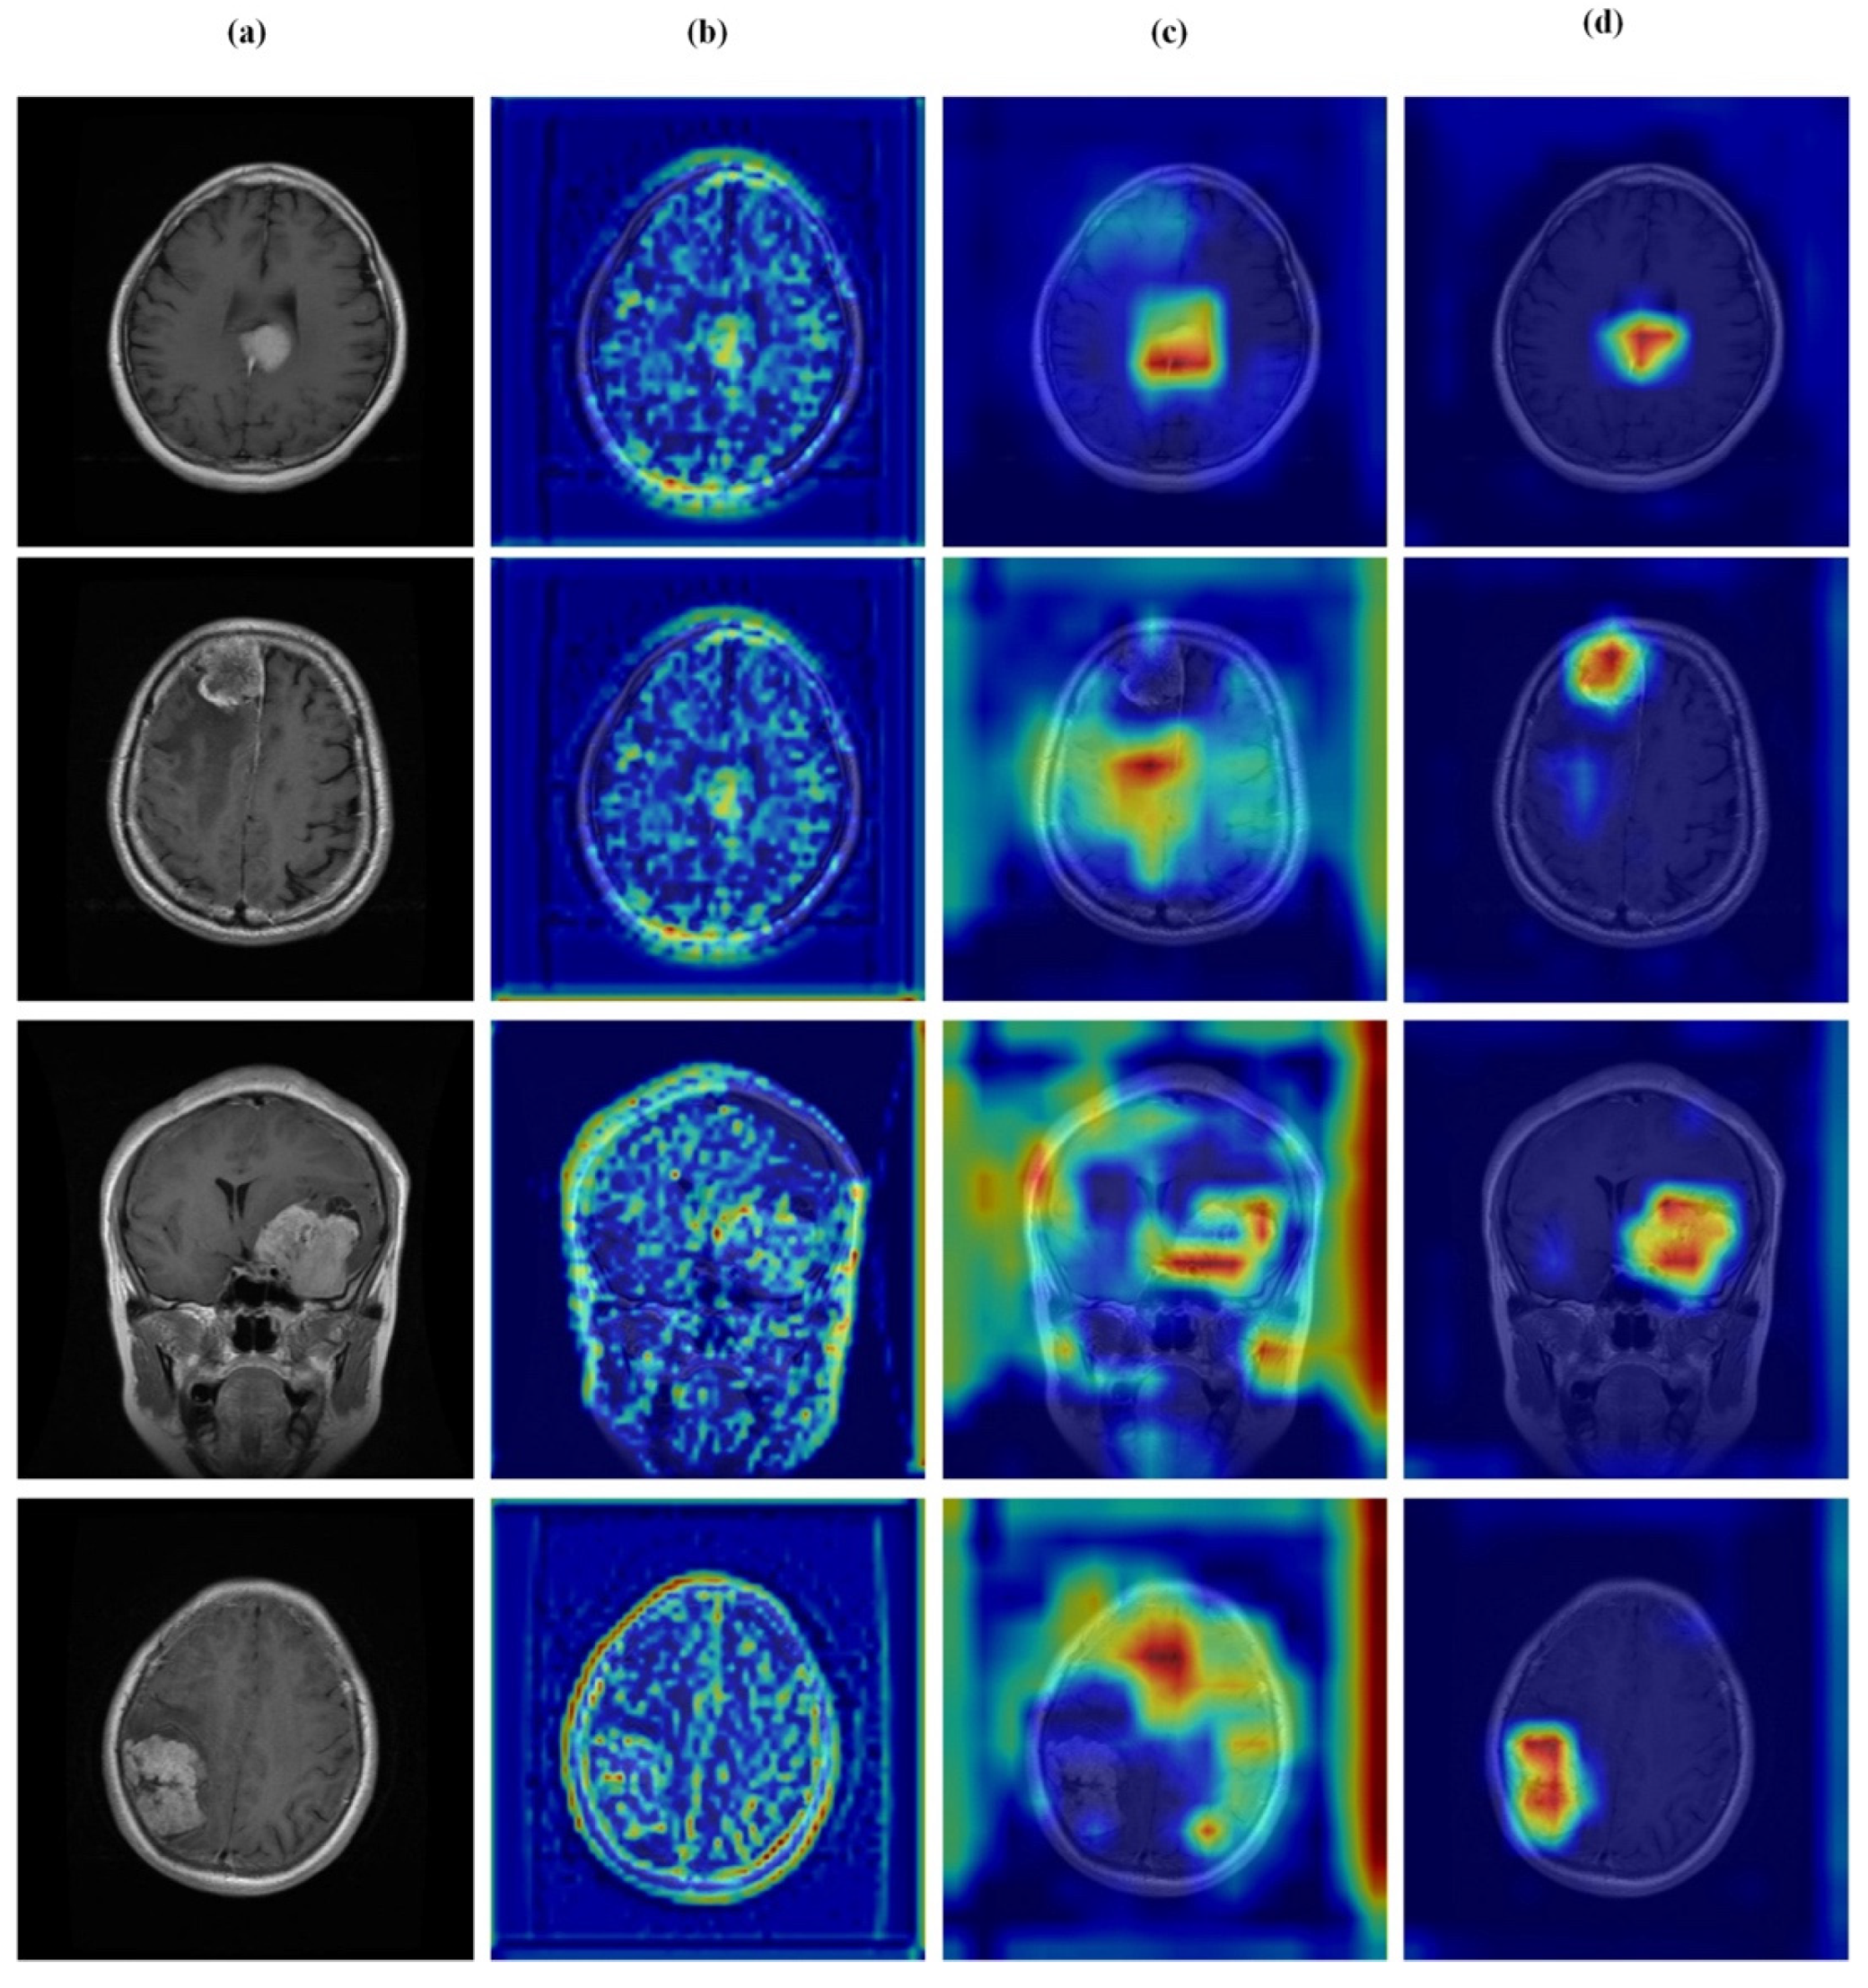

4.7. Feature Learning Analysis

Figure 12, Figure 13, Figure 14 and Figure 15 present Grad-CAM visualizations that trace the hierarchical feature learning of the proposed model across the four classes. Columns are organized as (a) input, (b) high-level features, (c) mid-level features, and (d) low-level features. In (d), the network emphasizes primitive cue edges, intensity transitions, and fine textures capturing sulcal boundaries, skull edges, and generic tissue patterns. Progressing to (c), activations become more structured and context-aware, highlighting coherent anatomical regions and diffuse hyperintense areas that provide spatial context for lesion localization. At (b), class-discriminative focus emerges with responses that contract tumor-centric hotspots for glioma and meningioma and to the sellar region for pituitary cases, while no_tumor images exhibit suppressed high-level responses, reflecting the model’s rejection of false lesion cues. This bottom-to-top progression from generic edges to task-specific evidence explains the model’s improved decision reliability and aligns with the multi-task design that encourages precise, clinically meaningful attention.

Visual representation of feature activations in glioma tumor cases. (a) input, (b) low-level features, (c) mid-level features, and (d) high-level features.

Figure 14.